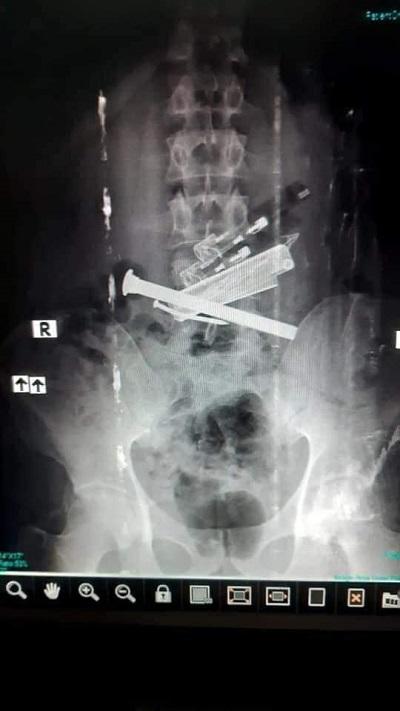

خبرني - نجح فريق طبي فلسطيني مختص باستخراج أشياء غريبة من بطن مريض فلسطيني في قطاع غزة.

ومن هذه الأشياء الغريبة مسمار كبير وقداحات واسلاك.